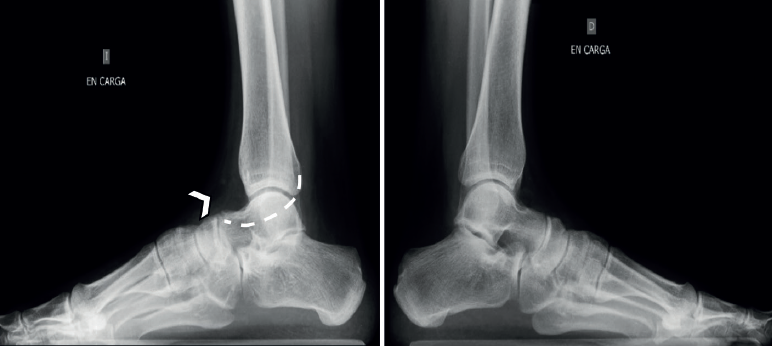

Las radiografías simples deben ser siempre bilaterales. Se deben solicitar: anteroposterior (AP) en carga, lateral en carga y oblicua a 45°. La radiografía a 45° descrita por Sloman en 1921(39) demuestra la presencia de coaliciones CN en el 90-100% de los casos(40,41). Es cierto que la superposición de los huesos del tarso dificulta el diagnóstico de la coalición, pero se han descrito algunos signos distintivos directos e indirectos que ayudan al diagnóstico, siendo los más conocidos el signo del oso hormiguero, el pico del astrágalo (talar beak) y el signo de la C. Estos signos clásicos muestran una buena especificidad, pero una sensibilidad moderada: el hecho de que la coalición sea fibrosa, cartilaginosa u ósea, y el tamaño variable de la coalición influirán en la imagen y en nuestra capacidad de diagnóstico.

El signo de la C o C-sign es el signo directo más fácil de identificar en la vista lateral. Analizando la faceta medial de la articulación subastragalina en las coaliciones TC, que son las más frecuentes (Figuras 7 y 8). Si es distrófico o la línea articular es irregular, sugiere osteoartritis. Los pacientes suelen ser jóvenes al diagnóstico. Posteriormente, en caso de sinostosis con continuidad entre el calcáneo y el astrágalo, un bloque óseo une la voluminosa faceta medial distrófica al sustentaculum tali. Tiene la forma de un arco convexo posteriormente: de ahí el “signo de la C”(45). En pies planos puede ser positivo sin coalición(46) (sensibilidad del 88% y especificidad del 87%)(22).

La ausencia de la faceta medial (subastragalina) precisa de una proyección exacta lateral centrada en el retropié(22). Si la articulación subastragalina posterior es visible y bien alineada, la anterior debiera ser igualmente visible; si no, es posible una coalición(22,47) (sensibilidad del 72-100% y especificidad del 42-94%) (Figura 8A).